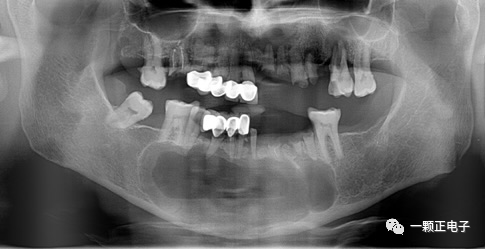

頜骨囊性病變(maxillarycysticdisease)是口腔頜面外科臨床常見疾病,其發(fā)病率高,主要表現(xiàn)為隱匿性頜骨破壞,無自限性生長,早期多無明顯自覺癥狀,患者多因局部面型改變、咬合紊亂、局部疼痛等就診。目前研究發(fā)現(xiàn)其形成的首要條件是頜骨胚胎發(fā)育時(shí)期殘留上皮,在感染、損傷等作用下,上皮增殖,調(diào)控因子異常表達(dá),囊腫形成。密閉的生長環(huán)境是囊腫發(fā)展的必要條件,囊壁不斷增殖液化,囊液滲透壓不斷增大,囊腔壓力持續(xù)升高,從而壓迫周圍骨質(zhì)膨脹吸收。1974年美國醫(yī)生Wine首次提出I期開窗減壓術(shù)治療頜骨巨大囊性病變,待病變縮小后II期刮除囊壁,并取得較好療效。開窗減壓術(shù)可以解除囊腔內(nèi)高壓,改變囊腔內(nèi)微環(huán)境,并制作囊腫塞維持開窗口形態(tài)及大小,促進(jìn)囊腔成骨過程,囊腔逐漸縮小,保存頜骨形態(tài)完整。目前成為國內(nèi)外臨床醫(yī)師治療頜骨巨大囊性病變首選的手術(shù)方式?;颊咔闆r:姓名:王某年齡:女22歲主訴:左下后牙不能咬合多年檢查:36頜面大面積齲壞,探診底穿,松動(dòng);I度,頰側(cè)牙齦稍腫脹,叩診(—);X線片:36殘冠,根尖周大面積透影區(qū),邊界清晰。診斷:頜骨囊腫頜骨囊性病變開窗減壓術(shù)治療后,持續(xù)維持囊腔通暢是手術(shù)成敗的關(guān)鍵,囊腫塞是其中的重要裝置。囊腫塞的主要作用包括:長期維持囊腔與口腔相通、保護(hù)囊腔衛(wèi)生,從而到達(dá)減壓的目的。囊腫塞的設(shè)計(jì)類似于隱形義齒或可摘局部義齒,能持續(xù)維持囊腔通暢引流,且患者能長期自行佩戴。